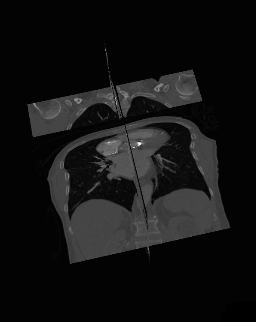

Magasabb dimenzióról beszélhetünk állóképek és mozgóképek esetén is. Egyszerű színes fotók is tekinthetők többdimenziós képnek, ha a harmadik dimenziónak a színcsatornákat (vagy a színkomponenseket tekintjük). További dimenziót jelenthet mozgókép esetében az eltelt idő. Az orvosi képalkotó (CT, MRI, fMRI) eszközök röntgen sugarakat bocsátanak ki, amelyek áthaladnak a vizsgált tárgyon vagy a páciens testén, majd egy fényérzékeny ernyőbe csapódnak be. Ezek az eszközök olyan 3D / 4D képet állítanak elő, amelyek denzitásképek vetülek sorozatából és rekonstrukciójából áll elő.